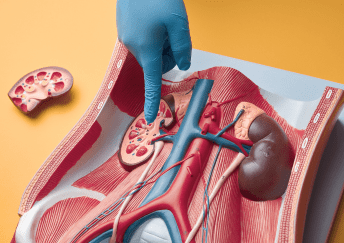

renal Sciences